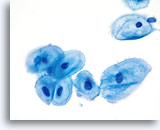

Atrophy

With the progression of atrophy during perimenopause and menopause there is a thinning of the epithelium, which often leads to a corresponding decrease in the number of cells shed during sample collection. Cell maturation is retarded, so that the prominent cell type becomes parabasal. With this shift in hormonal status the cell sample may contain increased glycogen, cellular degeneration and stripped nuclei. A granular background of degenerative cellular debris is generally seen. An inflammatory response is often present and evidence of bleeding is sometimes appreciated. Slight changes in the nuclear contours of the parabasal cells due to degeneration could lead to an over-diagnosis of atypia. It is important to evaluate nuclear size, the nuclear to cytoplasmic ratio and chromatin pattern carefully before rendering a cytologic diagnosis of ASC-US or more severe lesion in atrophic smears. In the case of atrophy with co-existing SIL, a sub-population of atypical cells should exhibit increased N/C ratios, hyperchromasia and irregular nuclear membranes.

Atrophy with inflammation

Conventional Pap smears from atrophic patients generally contain a uniform background of granular debris, and degenerated inflammatory cells. With ThinPrep slides this background debris is maintained, but is often pooled into small clumps alongside atrophic epithelium.